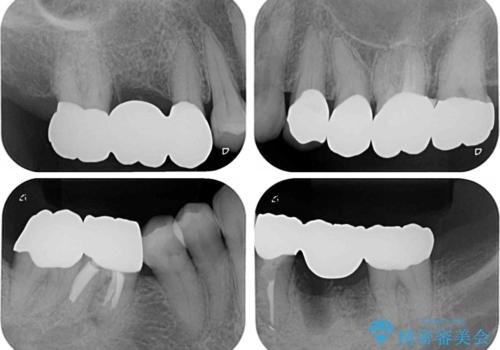

土台に含まれている金属も含め、口腔内の金属は全て除去し、抜歯しなければならない歯は抜歯し、オールセラミッククラウンやセラミックインレーにて治療することとしました。

上下奥歯の抜歯を同時期に行わず、下顎の治療を終えてから上顎を抜歯して治療を進めたため、1年ほどの期間を要しました。

口の中を一切気にしなくて良くなり、患者様には大変満足していただきました。